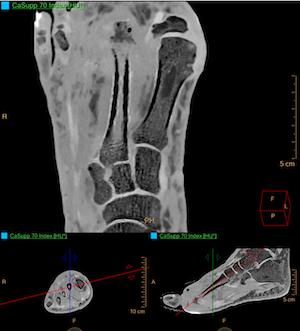

L’intelligence artificielle embarquée dans l’IQon garantit à chaque patient d’avoir un paramétrage adapté à sa morphologie afin de fournir la meilleure qualité image avec peu d’exposition aux rayons X, et d’éviter les examens inutiles ou inutilisables. L’IA améliore intelligemment le traitement et la transformation des informations en outils fonctionnels, comme la décomposition spectrale des rayons X et la reconstruction itérative des différentes énergies parfaitement dans l’espace des projections. Chaque élément de la matière répond ainsi de façon spécifique à une énergie donnée et, suivant le niveau de keV qui caractérise un rayonnement, il est ainsi possible d'étudier distinctement plusieurs matériaux comme le calcium pour les structures osseuses, ou encore l’iode injecté dans les vaisseaux, ou enfin dans des prises de contraste suspectes caractéristique d’une métastase par exemple.

Par une lisibilité accrue et immédiate, cette nouvelle imagerie apporte de la sérénité et de la confiance diagnostique. L’instantanéité du diagnostic, grâce à une résolution en contraste améliorée et sans bruit à n’importe quelle énergie, même pour les patients obèses, ou la suppression des artéfacts liés à la présence de prothèses métalliques notamment, améliore la prise en charge du patient.